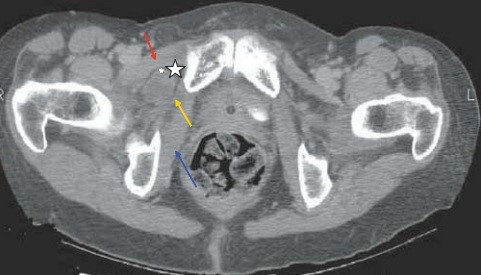

Bệnh nhân được chụp Xquang bụng: các quai ruột non giãn lớn kèm mức hơi dịch. Xquang phổi : hình ảnh dày thành kèm giãn phế quản dạng tổ ong (chụp nằm) (Hình 2). Siêu âm ổ bụng thấy hình ảnh giãn kèm tăng nhu động một số quai ruột non.

Hình 2. Xquang bụng và ngực

Chụp cắt lớp vi tính ổ bụng: các quai ruột non giãn kèm mức hơi dịch (h/a tắc ruột ). Hình ảnh quai ruột non chui qua lổ bịt trái. Dịch tư do ổ bụng lượng vừa. Tràn dịch màng phổi 2 bên lượng ít. (Hình 3).